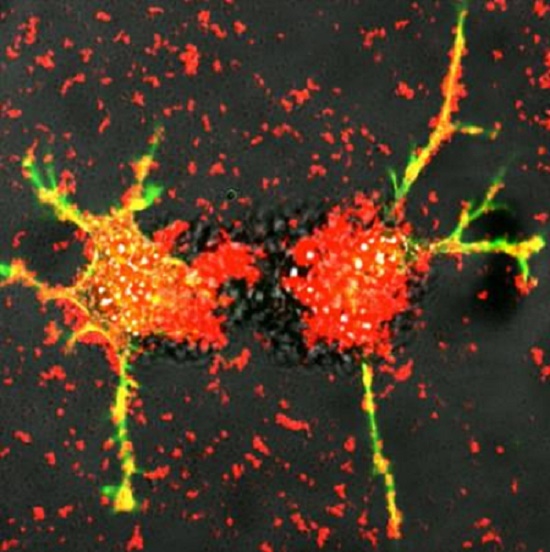

These are white blood cells reengineered by scientists at UNC-Chapel Hill deliver exosomes (red) loaded proteins that stimulate the growth of damaged nerve fibers (green and yellow). Researchers at the UNC Eshelman School of Pharmacy this technique can be developing into a potential treatment for Parkinson’s disease.

Image credit goes to: Elena Batrakova/UNC Eshelman School Of Pharmacy